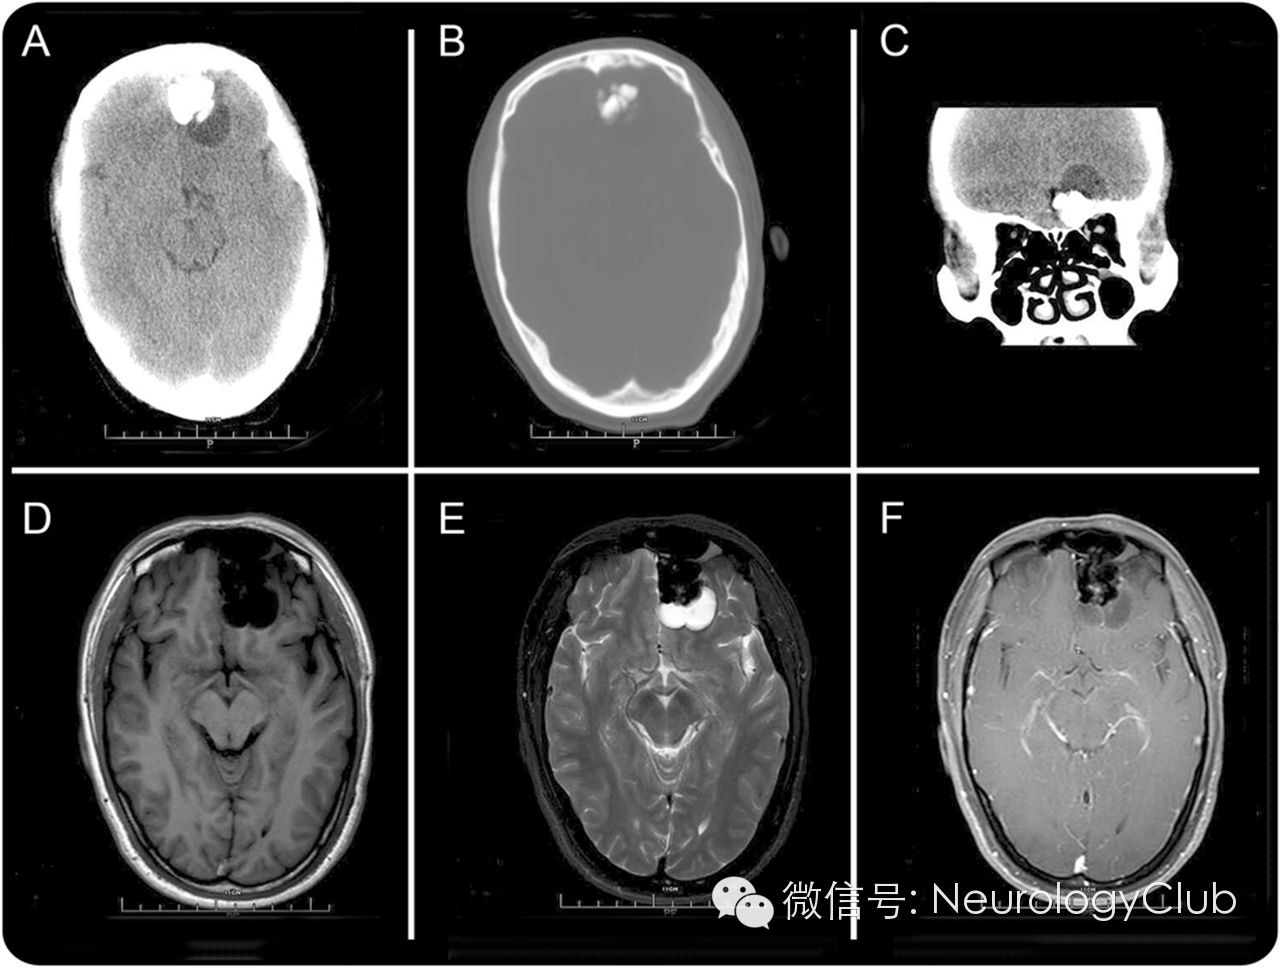

神经影像学如下:

(A-B:CT示肿块位于左侧颅前窝,伴钙化及囊变;C:CT冠状位肿块靠近筛窦;D-E:T1WI/T2WI示肿块形状不规则,信号混杂;F:增强示病灶边缘轻度强化)